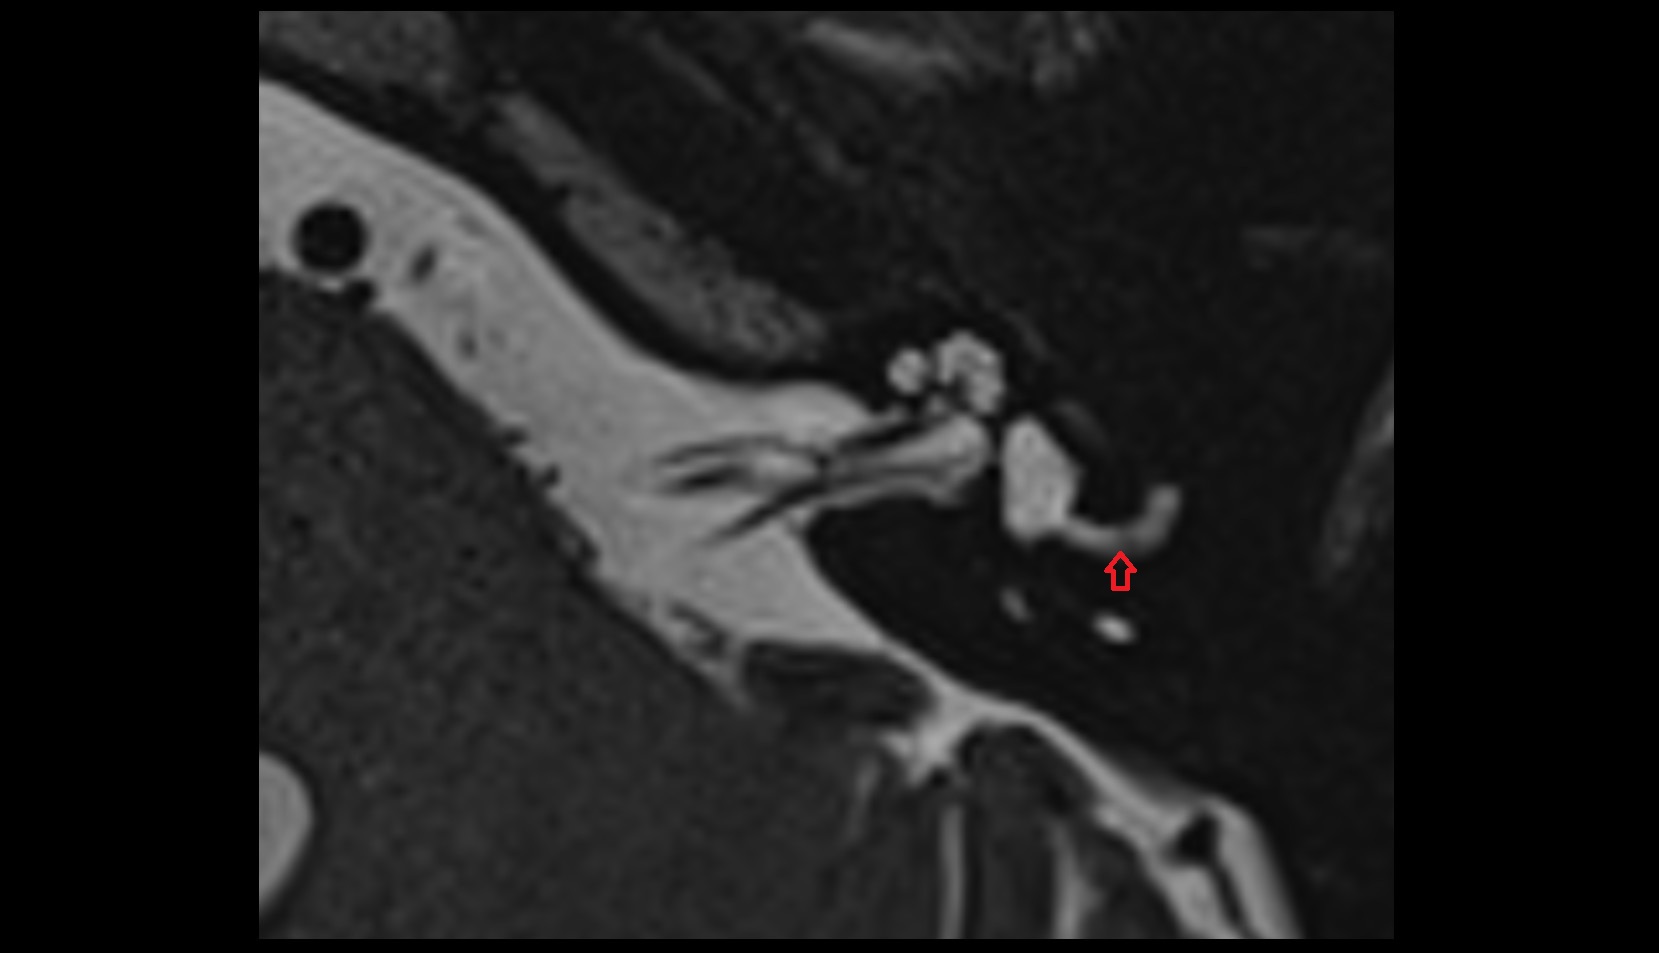

- Temporomandibular joint

- Articular disc of temporomandibular joint

- Articular eminence

- Mandibular condyle

- Mandibular fossa